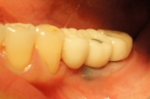

抜歯即時インプラント埋入・即時仮修復症例

奥歯三本が歯周病と根の破折で抜歯に。

入れ歯は絶対に嫌で歯がない期間があるのは困るとのご希望。

術前CT診断から後ろの二本なら抜歯直後にインプラント埋入が可能、後ろの一本は軽い骨移植が必要なので不可でしたが、前の一本は手術と同時に仮歯を入れることが可能と判断。

一度の処置で、抜歯・インプラント埋入・骨移植・仮歯まで行った症例。

抜歯後に骨移植を行いインプラントを入れる方法では治療期間が7~8か月かかるところをこの方法にしたので、入れ歯も使わずに治療期間を4か月に短縮できました。

被せ物の色は後日ホワイトニングを行うので白めにしています。